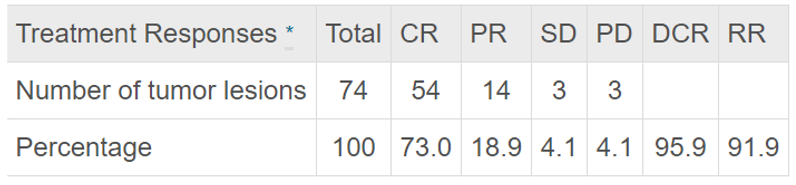

① 术后 1 月肿瘤治疗反应:冷冻消融术后一个月肿瘤疾病控制率达95.9%。